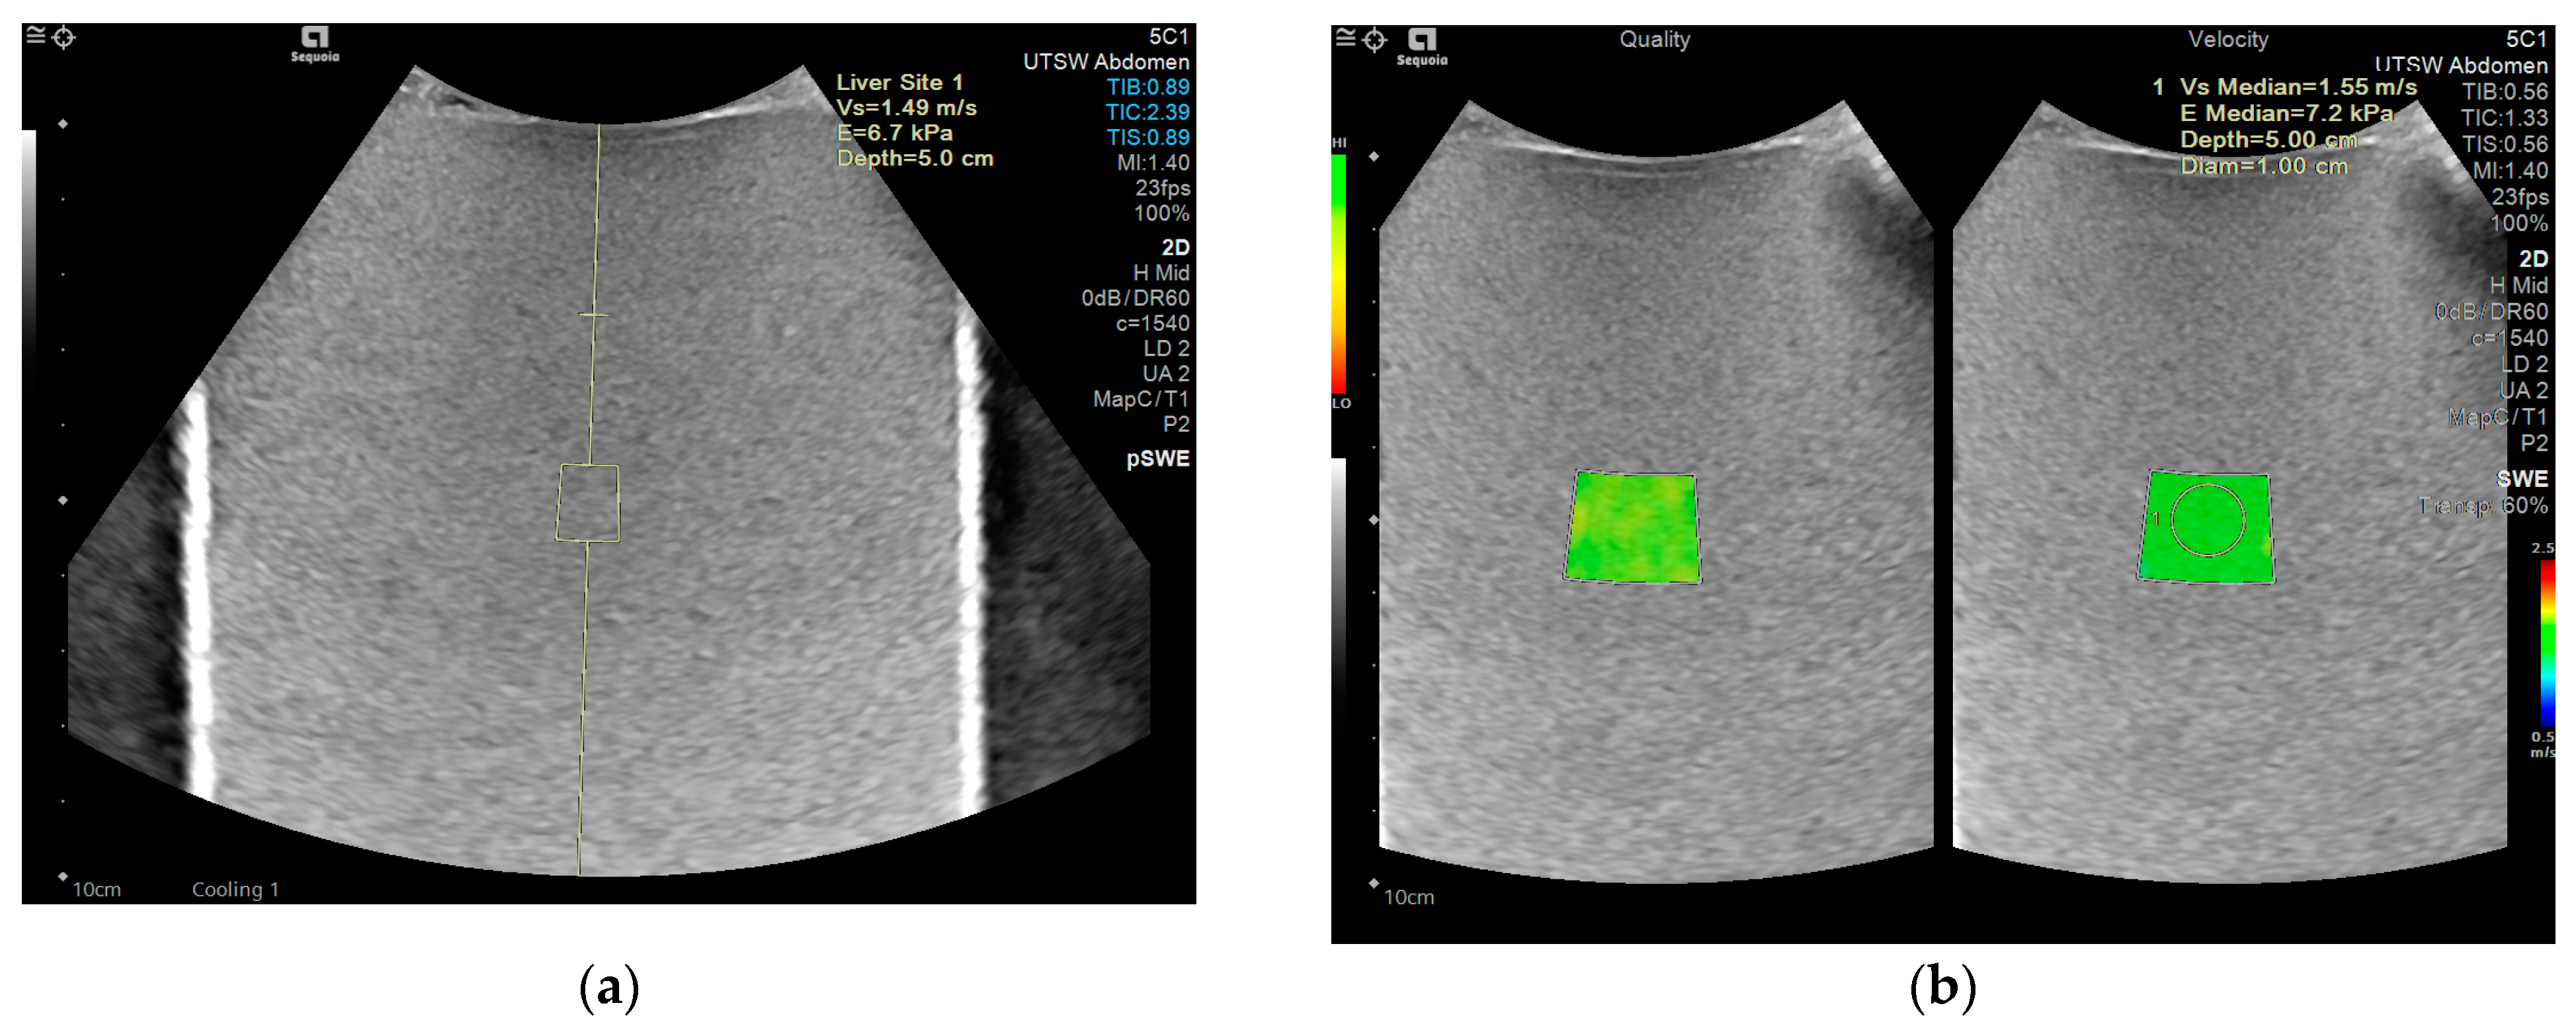

| Equipment (Model) | Software Version | Probe | Acquisition | Anthropomorphic Abdominal Phantom | Shear Wave Liver Phantoms |

|---|---|---|---|---|---|

| GE (Logiq E10) | R3 | C1-6 | 2D shear wave | x | x |

| Philips (Epic 5G) | 9.0 | C5-1 | Point and 2D shear wave | x | x |

| Siemens (Sequoia) | VA40A | 5C1 | Point and 2D shear wave | x | x |